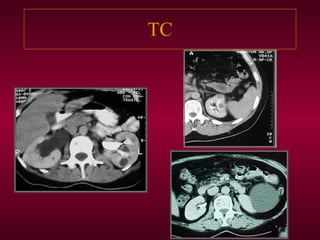

TC  RM  Densidad agua alta densidad: proteinas s.pico,borde fino finos tabiques no capta cte. Calcif. periféricas Hiperintensos en T2 hipointensos en T1 hiperintensos T1:prot. No capta Gado Confiabilidad cercana al 100%(todos los métodos)

TC